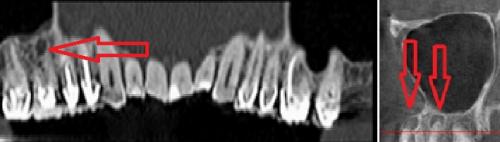

![]() | ![]() | ![]() |

| Выход пломбировочного материала за верхушку зуба вызывал жестокие боли во второй ветви тройничного нерва у мужчины. Вид сбоку:

зуба, кружком обведен | Стреляющая боль во всех трех ветвях была следствием плохого кровообращения в мозговых отделах тройничного нерва у пожилой женщины. Кружком обведен участок мозга, пострадавший от закупорки одного из сосудов головного мозга. Проверить сосуды головы и шеи | Невралгия тройничного нерва была у молодой женщины из-за давления одной из мозговых артерий на корешок тройничного нерва. На МР-томограмме видно пересечение тройничного нерва (идет вертикально) с артерией (идет горизонтально). Артерия оказывала давление на тройничный нерв в месте его выхода из ствола мозга. |

Стрелками показаны фрагменты пломбировочного материала (вид спереди и сбоку), который при пломбировании канала выпал за пределы зуба и «упёрся» в область залегания ветви тройничного нерва. У пациента долго болел зуб после лечения пульпита, затем онемела верхняя губа и часть щеки.

Стрелками показаны кисты корней зубов (вид спереди). Кисты в данном случае представляют собой замкнутые очаги инфекционного воспаления. Киста со временем набухает и создает давление на ветви тройничного нерва, отсюда онемение лица и боль. Осложнение после лечения пульпита.

2. Рентгеновские исследования. На обычных рентгенограммах и панорамных снимках не всегда видна истинная картина болезни. Мы рекомендуем конусно-лучевую компьютерную томографию с функцией защиты от дефектов изображения от пломбировочного материала и протезов.